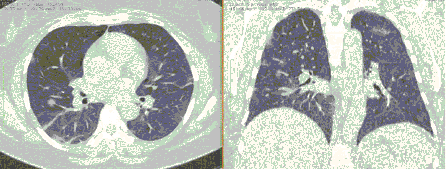

4.3. ЛУЧЕВАЯ ДИАГНОСТИКА COVID-19

Методы лучевой диагностики применяют для выявления COVID-19 пневмоний, их осложнений, дифференциальной диагностики с другими заболеваниями легких, а также для определения степени выраженности и динамики изменений, оценки эффективности проводимой терапии.

К методам лучевой диагностики патологии ОГК пациентов с предполагаемой/установленной COVID-19 пневмонией относят:

- Компьютерную томографию легких (КТ),

КТ имеет высокую чувствительность в выявлении изменений в легких, характерных для COVID-19. Применение КТ целесообразно для первичной оценки состояния ОГК у пациентов с тяжелыми прогрессирующими формами заболевания, а также для дифференциальной диагностики выявленных изменений и оценки динамики процесса. КТ позволяет выявить характерные изменения в легких у пациентов с COVID-19 еще до появления положительных лабораторных тестов на инфекцию с помощью МАНК. В то же время, КТ выявляет изменения легких у значительного числа пациентов с бессимптомной и легкой формами заболевания, которым не требуется госпитализация. Результаты КТ в этих случаях не влияют на тактику лечения и прогноз заболевания при наличии лабораторного подтверждения COVID-19. Поэтому массовое применение КТ для скрининга асимптомных и легких форм болезни не рекомендуется. При первичном обращении пациента с подозрением на COVID-19 рекомендуется назначать КТ только при наличии клинических и инструментальных признаков дыхательной недостаточности (SpO2 < 95%, ЧДД > 22).

4. Все выявляемые при лучевых исследованиях признаки, включая КТ-симптомы, не являются специфичными для какого-либо вида инфекции и не позволяют установить этиологический диагноз. Вне клинической (эпидемической) ситуации они не позволяют отнести выявленные изменения к пневмонии COVID-19 и дифференцировать их с другими пневмониями и невоспалительными заболеваниями. Данные лучевого исследования не заменяют результаты обследования на РНК SARS-CoV-2. Отсутствие изменений при КТ не исключает наличие COVID-19 и возможность развития пневмонии после проведения исследования.